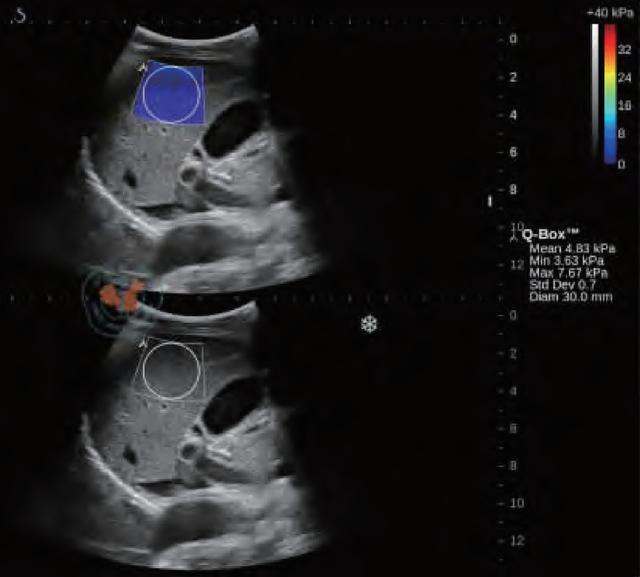

辐射对肌肉的影响,人体肌肉会变得怎么样呢

图12 慢性肝病患者的肝脏剪切波弹性成像及定量分析图。下图是原始的成像图,上图的蓝色区域则是在成像区域内选取直径为3 mm的圆形定量检测区域进行弹性模量的检测

谐波运动成像最早由Maleke等人提出。通过探头产生的超声波对组织施加周期性的声辐射力,使组织产生谐波运动。通过获取组织被激发前后的B超图像并对其进行运动估计,可以间接反映组织的弹性状况。该方法可以准确反映深部组织的局部弹性状况,但由于需要在激发信号的同时监测组织的运动,因而采集到的B超信号容易受到激发信号的严重干扰,这是该成像方法迄今为止尚未得到完美解决的主要问题。当声辐射力作用在组织上时会激发出剪切波,剪切波弹性成像正是通过检测这一剪切波的传播来达到成像的目的,最早由美国学者Sarvazyan和Emelianov提出。他们利用高强度聚焦超声探头产生声辐射力,在人体组织中产生了明显的剪切波,并运用磁共振成像方法监测该剪切波的传播情况。由于剪切波速与人体组织的粘弹特性紧密相关,因此通过检测剪切波的传播速度等参数可以获取组织的弹性信息。图12显示了某一慢性肝病患者的肝脏弹性成像图。声辐射力脉冲成像技术最早由杜克大学的学者Nightingale等人提出,该方法通过高能聚焦超声探头在局部组织中产生短暂的高强度声辐射力,从而推动组织产生一定的应变,再通过追踪这些微小应变和剪切波的传播来判断组织的粘弹特性。研究人员发现,组织对于脉冲声辐射力的瞬态响应直接相关于局部区域的硬度大小,而通过求解亥姆霍兹方程的反问题方法可以量化组织中剪切波的波速。Nightingale等通过详细的数值仿真和体模研究证实了声辐射力脉冲成像的可行性,并得到了与传统B超图像相比更高的对比度和分辨力。如今的声辐射力脉冲成像已在临床上具备多种脏器检查的能力,图13显示了某位良性纤维瘤患者的乳腺声辐射力脉冲成像图。